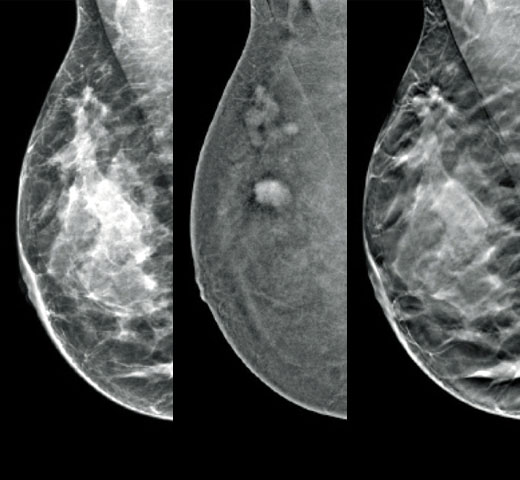

Screening og diagnose